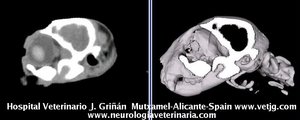

imágenes de TC en el gato | |||||||||||

Click aquí para ver reconstrucciones en 3D a partir de imágenes de TC |

Mismo paciente: Correspondencias entre el corte sagital y el volumen, ambos reconstruidos a partir de imágenes TC (transversales) |